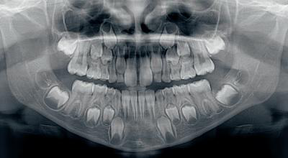

Dzięki zastosowaniu w radiowizjografii cyfrowej szybkiego złącza USB2, obraz pojawia się w czasie poniżej 2 sekund.

Dzięki radiowizjografii dentysta jest w stanie ocenić długość kanału zęba, gęstość kości, poprawność wypełnienia kanału itp.

Dzięki temu badaniu, można wykryć wczesne stadium najczęściej występującej choroby zębów - próchnicy.

Zaletą radiowizjografii cyfrowej jest zredukowanie dawki promieniowania o około 90% w stosunku do zdjęcia klasycznego.